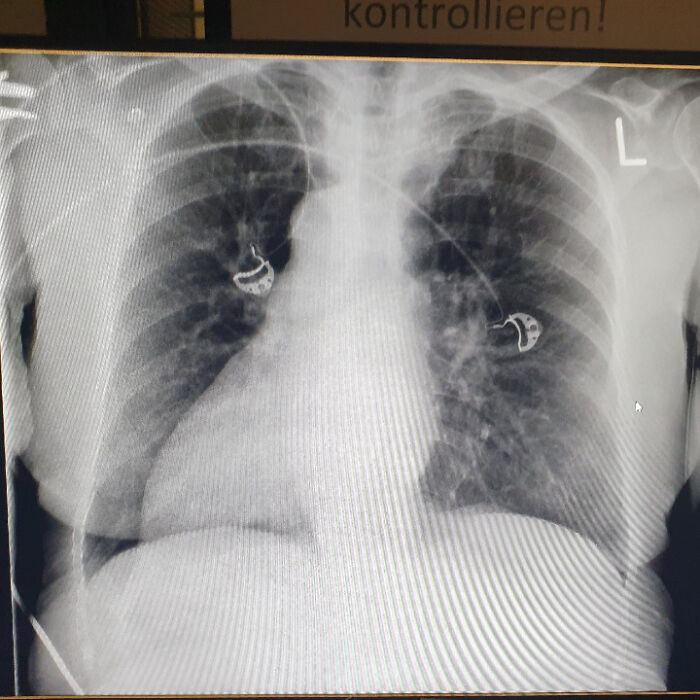

In college dissection, the cadaver’s pacemaker went off every class, sounding like an ambulance. His heart was so enlarged it shoved his whole left lung beneath it. Also, found another guy with 4 lobes on his right lung instead of 3. Anatomy surprises on every level!